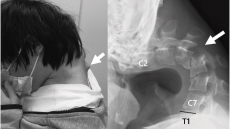

Ένας 25χρονος στην Ιαπωνία «στράβωσε» τον αυχένα του επειδή χρησιμοποιούσε για χρόνια σκυφτός το κινητό του - Ο νεαρός είχε φτάσει σε σημείο να μην μπορεί να φάει, λόγω της στάσης του

Ιαπωνία: Ένας 25χρονος στράβωσε τον αυχένα του επειδή χρησιμοποιούσε για χρόνια σκυφτός το κινητό του

Πρόκειται για το σύνδρομο πτώσης κεφαλής - Ο νεαρός είχε φτάσει σε σημείο να μην μπορεί να φάει σωστά, λόγω της στάσης του - Πώς αντιμετωπίστηκε η περίπτωσή του